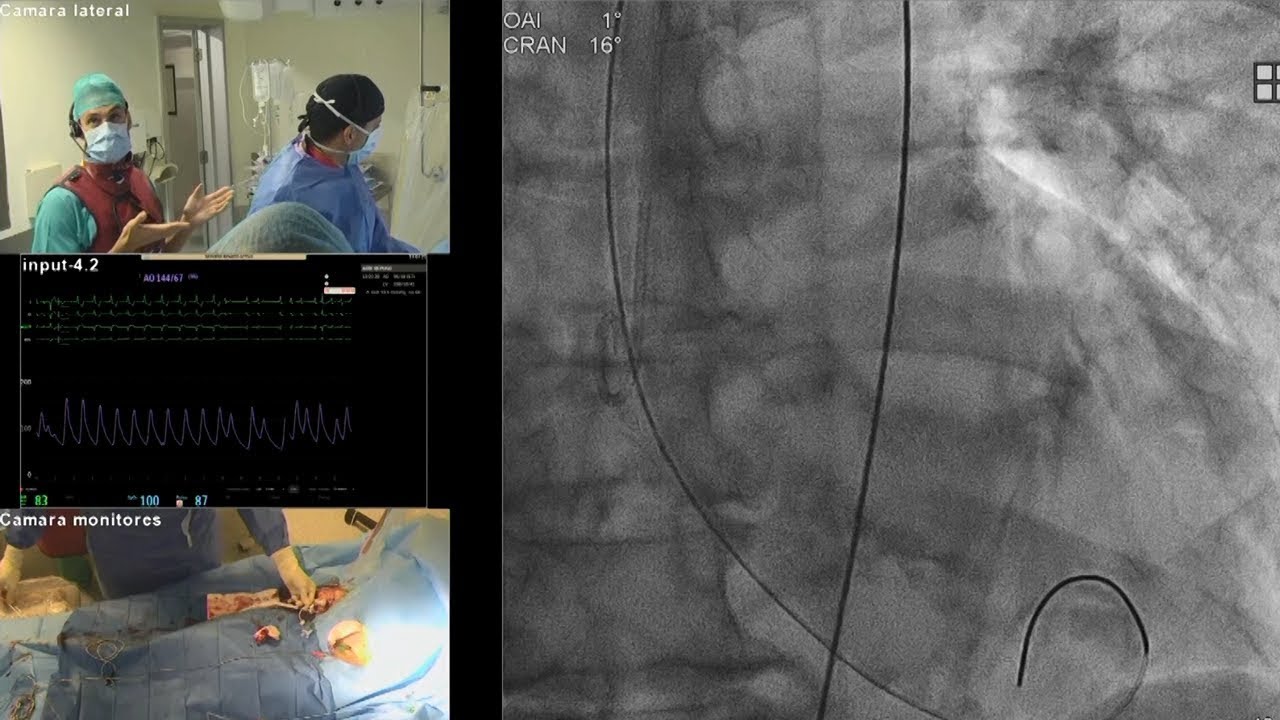

Complex PCI for stent failure: LIVE Educational Case from Hospital Clínico San Carlos - Madrid, Spain

Complex multivessel disease: LIVE Educational Case from Hospital Clínico San Carlos - Madrid, Spain

Complex PCI in a TAVI patient: Opening LIVE Educational Case from Clinique Pasteur - Toulouse, France

Complex PCI in calcific coronary artery disease: LIVE Educational Case from Clinique Pasteur - Toulouse, France